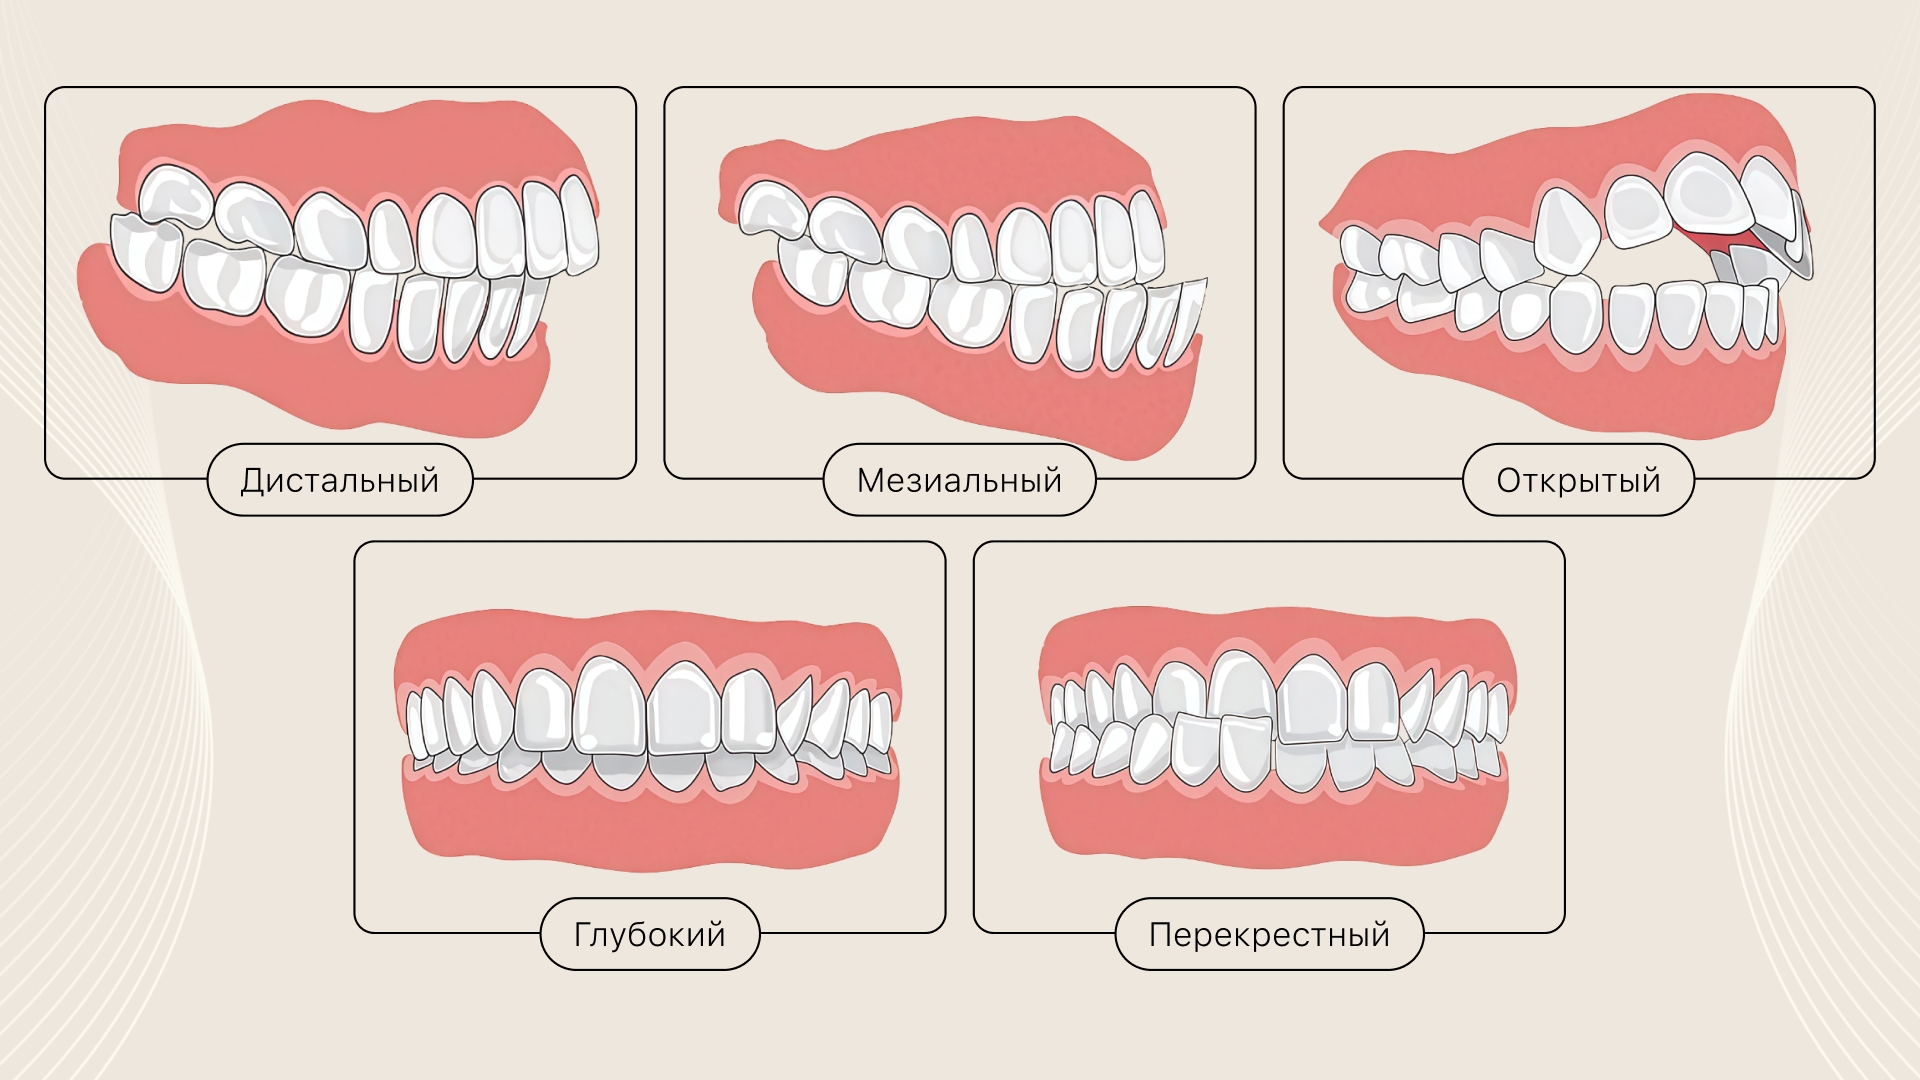

Дистальный

Чрезмерно развитая верхняя челюсть, или недоразвитая нижняя челюсть.

- передние зубы(резцы) верхней челюсти выступают;

- искажены черты лица — невыраженный подбородок.

Мезиальный

Нижняя челюсть выступает вперёд, верхняя челюсть недоразвита.

- резцы верхней челюсти частично или почти полностью перекрыты нижними;

- чрезмерно выступает подбородок;

- между передними зубами верхней и нижней челюсти выраженно расстояние, в большей или меньшей степени.

Перекрёстный

Данная патология часто сопровождается асимметрией лица.

- улыбка выглядит некрасиво;

- при смыкании происходит пересечение зубных рядов, то есть перекрестное смыкание;

- могут появляться дефекты дикции.

Глубокий

Зубы верхнег�о зубного ряда полностью перекрывают нижние.

- травмируются мягкие ткани полости рта;

- нарушены пропорции лица, из-за снижения высоты прикуса.

Открытый

При данной патологии смыкаются только боковые зубы.

- между верхними и нижними передними зубами есть расстояние различной степени выраженности, контакты между зубами отсутствуют;

- визуально может складываться впечатление, что рот постоянно открыт.